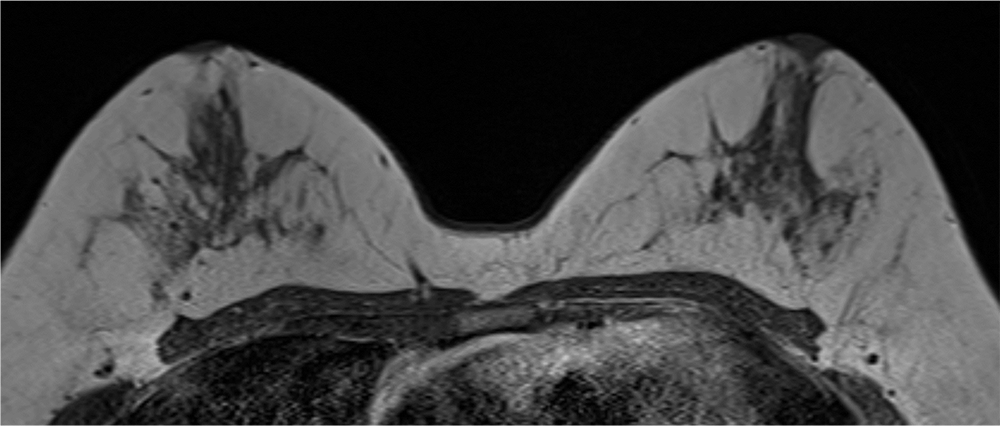

6. 造影後高分解能画像

区域性分布を示すNon mass enhancementがあるようにも見えるが、同定は困難である。